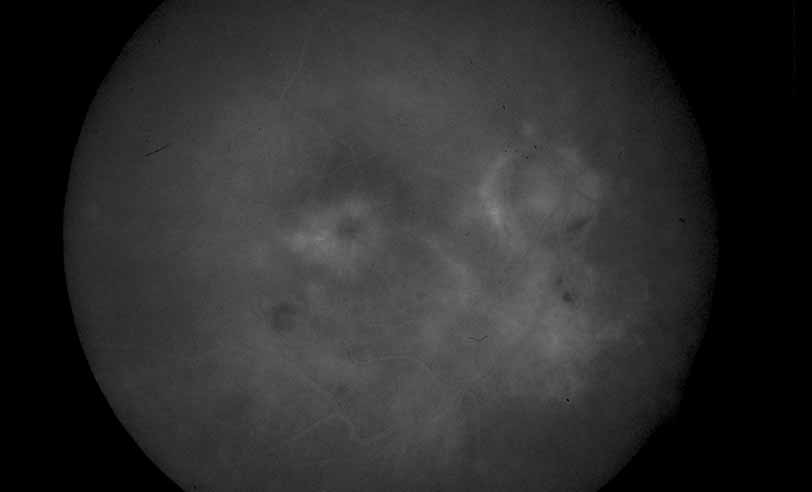

Fig. 28 Serpiginous choroiditis. ICG angiography early frame shows multiple hypofluorescent spots in the location of the lesions seen on color photography.